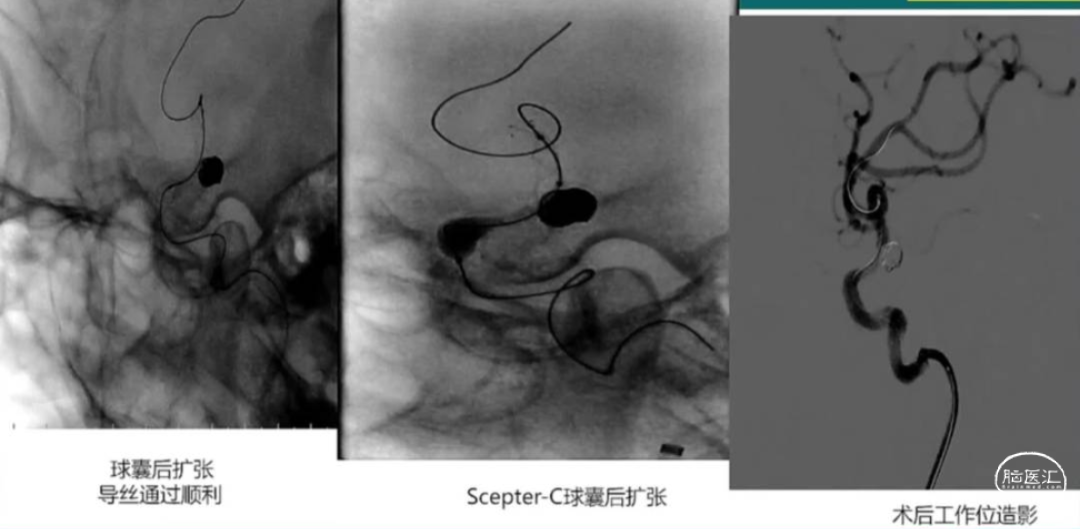

(四步法,3米导丝,交换多次)

长鞘 7F-90

中间导管 6F-115cm

微导丝 0.014--3m

Gateway球囊 2.0mm*15mm (预扩张)

-21支架微导管

0.014-微导管

支架 3.5mm*20mm

弹簧圈:

Scepter-C球囊 (后扩张)